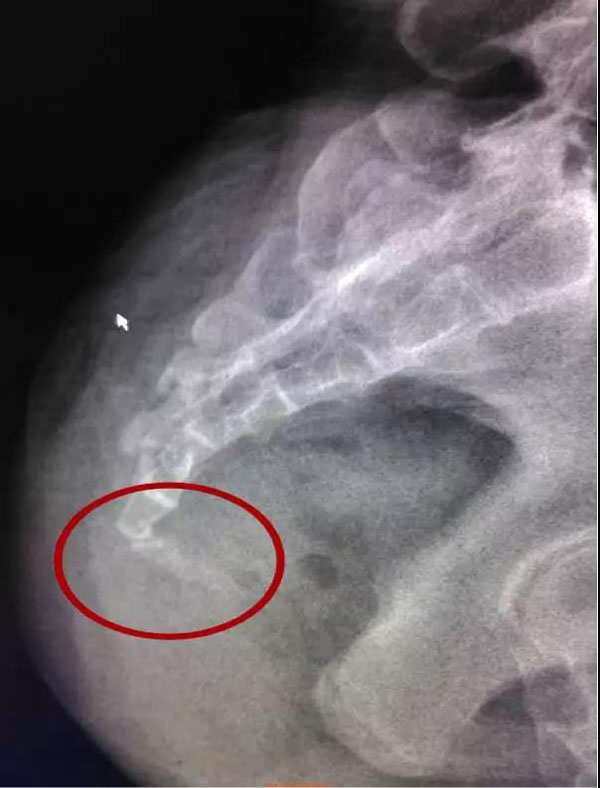

قۇيرۇق سۆڭەك(尾骨) ۋە توققۇز كۆز سۆڭەك(骶骨)، داس سۆڭەك بوشلۇقىنىڭ "ئارقا ھويلا تېمى"نى تەشكىل قىلىدىغان بولۇپ، قۇيرۇق سۆڭەك بىلەن توققۇز كۆز سۆڭەك بىرلىشىپ، ئوتتۇرلۇقتا پەقەت ئىنتايىن نىپىز ھەم سۈزۈك بولغان بىر پارچە كۈمۈرچەك ئايرىپ تۇرىدىغان ھەمدە ئاساسى جەھەتتىن ھەرىكەتلىنەلمەيدىغان، قۇيرۇق-توققۇز كۆز بوغۇمىنى شەكىللەندۈرگەن. بىراق، ھامىلدارلىق بوشىتىش ھورمۇنىنىڭ تەسىرى ئاستىدا، قۇيرۇق-توققۇز كۆز بوغۇمىنىڭ ھەرىكەتچانلىقى كۆرۈنەرلىك دەرىجىدە ئاشىدۇ، بۇنىڭدا قۇيرۇق سۆڭەك تۇغۇت جەريانىدا بالىنىڭ تۇغۇلىشىغا توسقۇنلۇق قىلىۋالمايدىغان بولىدۇ. تۇغۇتتىن كىيىنكى نەچچە ئاي ئىچىدە، قۇيرۇق-توققۇز كۆز بوغۇمى قايتىدىن قېتىشىدۇ؛ بۇندىن باشقا، ياشنىڭ ئېشىشىغا ئەگىشىپ، قۇيرۇق-توققۇز كۆز بوغۇمى ئارىسىدىكى سۈزۈك كۈمۈرچەكمۇ ئۆزلىكىدىن يوقايدىغان بولۇپ، قۇيرۇق سۆڭەك بىلەن توققۇز كۆز سۆڭەك پۈتۈنلەي بىرلىشىپ كىتىدۇ.

شۇڭا، تۇغۇتتىن كىيىنكى بۇ ئالاھىدە مەزگىلدە، قۇيرۇق-توققۇز كۆز بوغۇمى بوشىشىپ كىتىدىغان بولغاچقا، قوساق قاتلاش ھەرىكىتى، بەدەننىڭ ئۈستى قىسمى بىلەن ئاستى قىسمىنىڭ، قۇيرۇق-توققۇز كۆز بوغۇمى قىسىمدا قاتلىنىشىنى شەكىللەندۈرىدۇ؛ بولۇپمۇ نىسبەتەن قاتتىقراق بولغان يەر يۈزىدە قوساق قاتلاش ھەرىكىتى ئىشلىگەندە، ئاسانلا قۇيرۇق سۆڭەكنىڭ سۇنۇپ كىتىشىنى ياكى قۇيرۇق سۆڭەكنىڭ بۇ بوغۇم ئىچىدىكى ئىلىنچۈكنىڭ ئورنىنىڭ يۆتكىلىپ كىتىشىنى كەلتۈرۈپ چىقرىدىغان بولۇپ، قاتتىق ئاغرىق پەيدا قىلىدۇ، ھەتتا ئولتۇرالماسلىق ۋە ئۆرە تۇرالماسلىقنى كەلتۈرۈپ چىقىرىدۇ.

قۇيرۇق سۆڭەكنىڭ ئالدى تەرەپ، مەقئەت بىلەن تۈز ئۈچەي؛ ئەگەر قۇيرۇق سۆڭەك ئىچكى ئلىنچۈكىنىڭ ئورنى يۆتكىلىپ كەتسە ياكى قۇيرۇق سۆڭەك سۇنۇپ كەتسە، چوڭ تەرەت قىلىشقا تەسىر كۆرسىتىپ، قەۋزىيەتنى كەلتۈرۈپ چىقىرىدۇ.

قۇيرۇق-توققۇز كۆز بوغۇمى ئورنى، داس سۆڭەك بوشلۇقى مۇسكۇللىرى توپى ئاساسلىق ئورۇنلاشقان ئورۇن بولۇپ، قۇيرۇق-توققۇز كۆز بوغۇم سۇنسا ياكى ئورنى يۆتكىلىپ كەتسە، قۇيرۇق-توققۇز كۆز بوغۇمىنىڭ مەڭگۈلۈك شەكلى ئۆزگىرىپ كىتىشىنى پەيدا قىلىپ، تۇغۇتتىن كىيىنكى داس سۆڭەك بوشلۇقى مۇسكۇللىرىنىڭ ئەسلىگە كىلىشىگە تەسىر كۆرسىتىشى مۇمكىن.